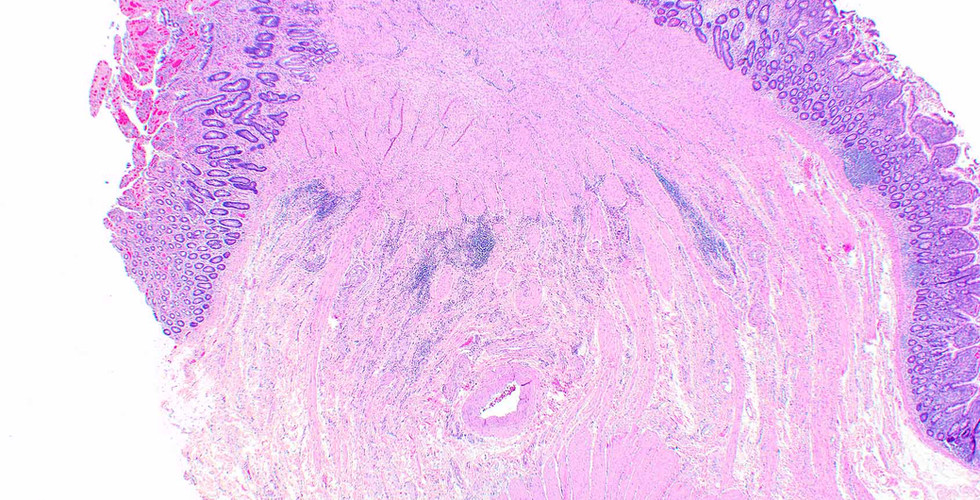

This lesion arose in the small intestine, resulting in obstruction and probably was related to use of non-steroidal anti-inflammatory drugs.

Cortina G, Wren S, Armstrong B, Lewin K, Fajardo L. Clinical and pathologic overlap in nonsteroidal anti-inflammatory drug-related small bowel diaphragm disease and the neuromuscular and vascular hamartoma of the small bowel. Am J Surg Pathol. 1999 Nov;23(11):1414-7. www.innovativsciencepress.com